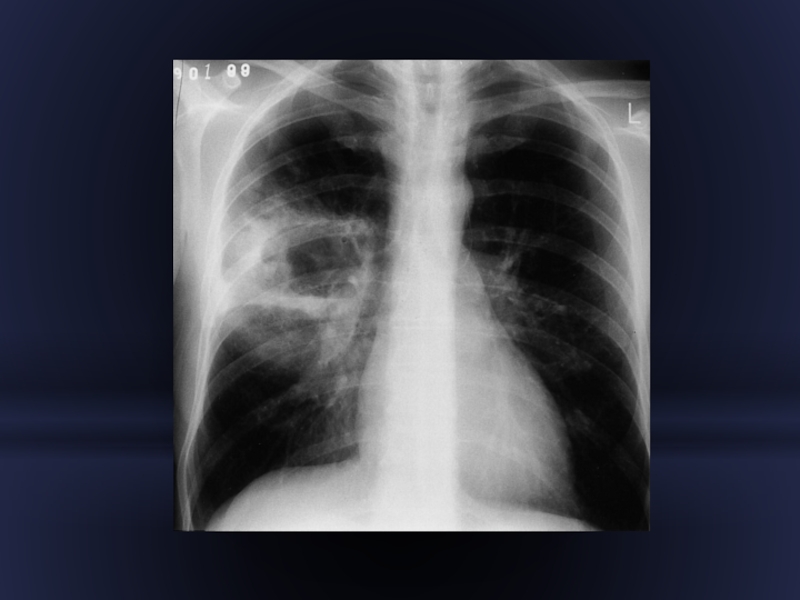

Слайд 35Пневмонія

Ділянка затемнення з вузькими світлими смужками бронхів, з чітким

кордоном, що збігається з міждолевою плеврою, межа затемнення, що не є прилеглою до плеври має розмиті контури.